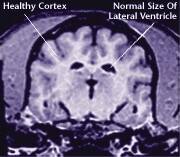

Just like the rest of the body, the brain is affected by the aging process. Damage to the brain’s cells can lead to changes in your dog’s behavior and alertness.

It's important to remember that aging is a natural part of your dog's life. Half of all dogs 8 years and older will show some signs of brain aging, and as your dog ages, he may begin to act differently. Thanks to advances in medicine and pet nutrition, the right dog food and veterinary advice can help limit the effects of brain aging and maintain your dog’s activity level.

Aging takes a toll on a dog's entire body, including his brain. In recent years, scientists have made great strides in understanding the aging process. Today, many experts agree that aging is primarily caused by unstable oxygen molecules called free radicals. As the brain ages, free radicals cause damage to the cells. Although some free radicals may be caused by the effects of environmental conditions, the majority are produced by the body’s own metabolism.

The aging process attacks all body systems and organs in a dog, including the brain. The result is a loss of brain function, and often, the appearance of behavioral changes that were not present in a dog’s younger years.

MRI scans show loss of brain tissue in affected dogs. Note: MRI scans are not harmful to dogs. |